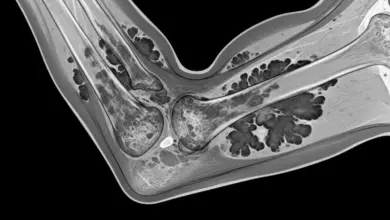

Condromatose sinovial do cotovelo: o que é

A condromatose sinovial do cotovelo ocorre quando a sinóvia, tecido que reveste internamente a articulação, sofre uma alteração e passa…